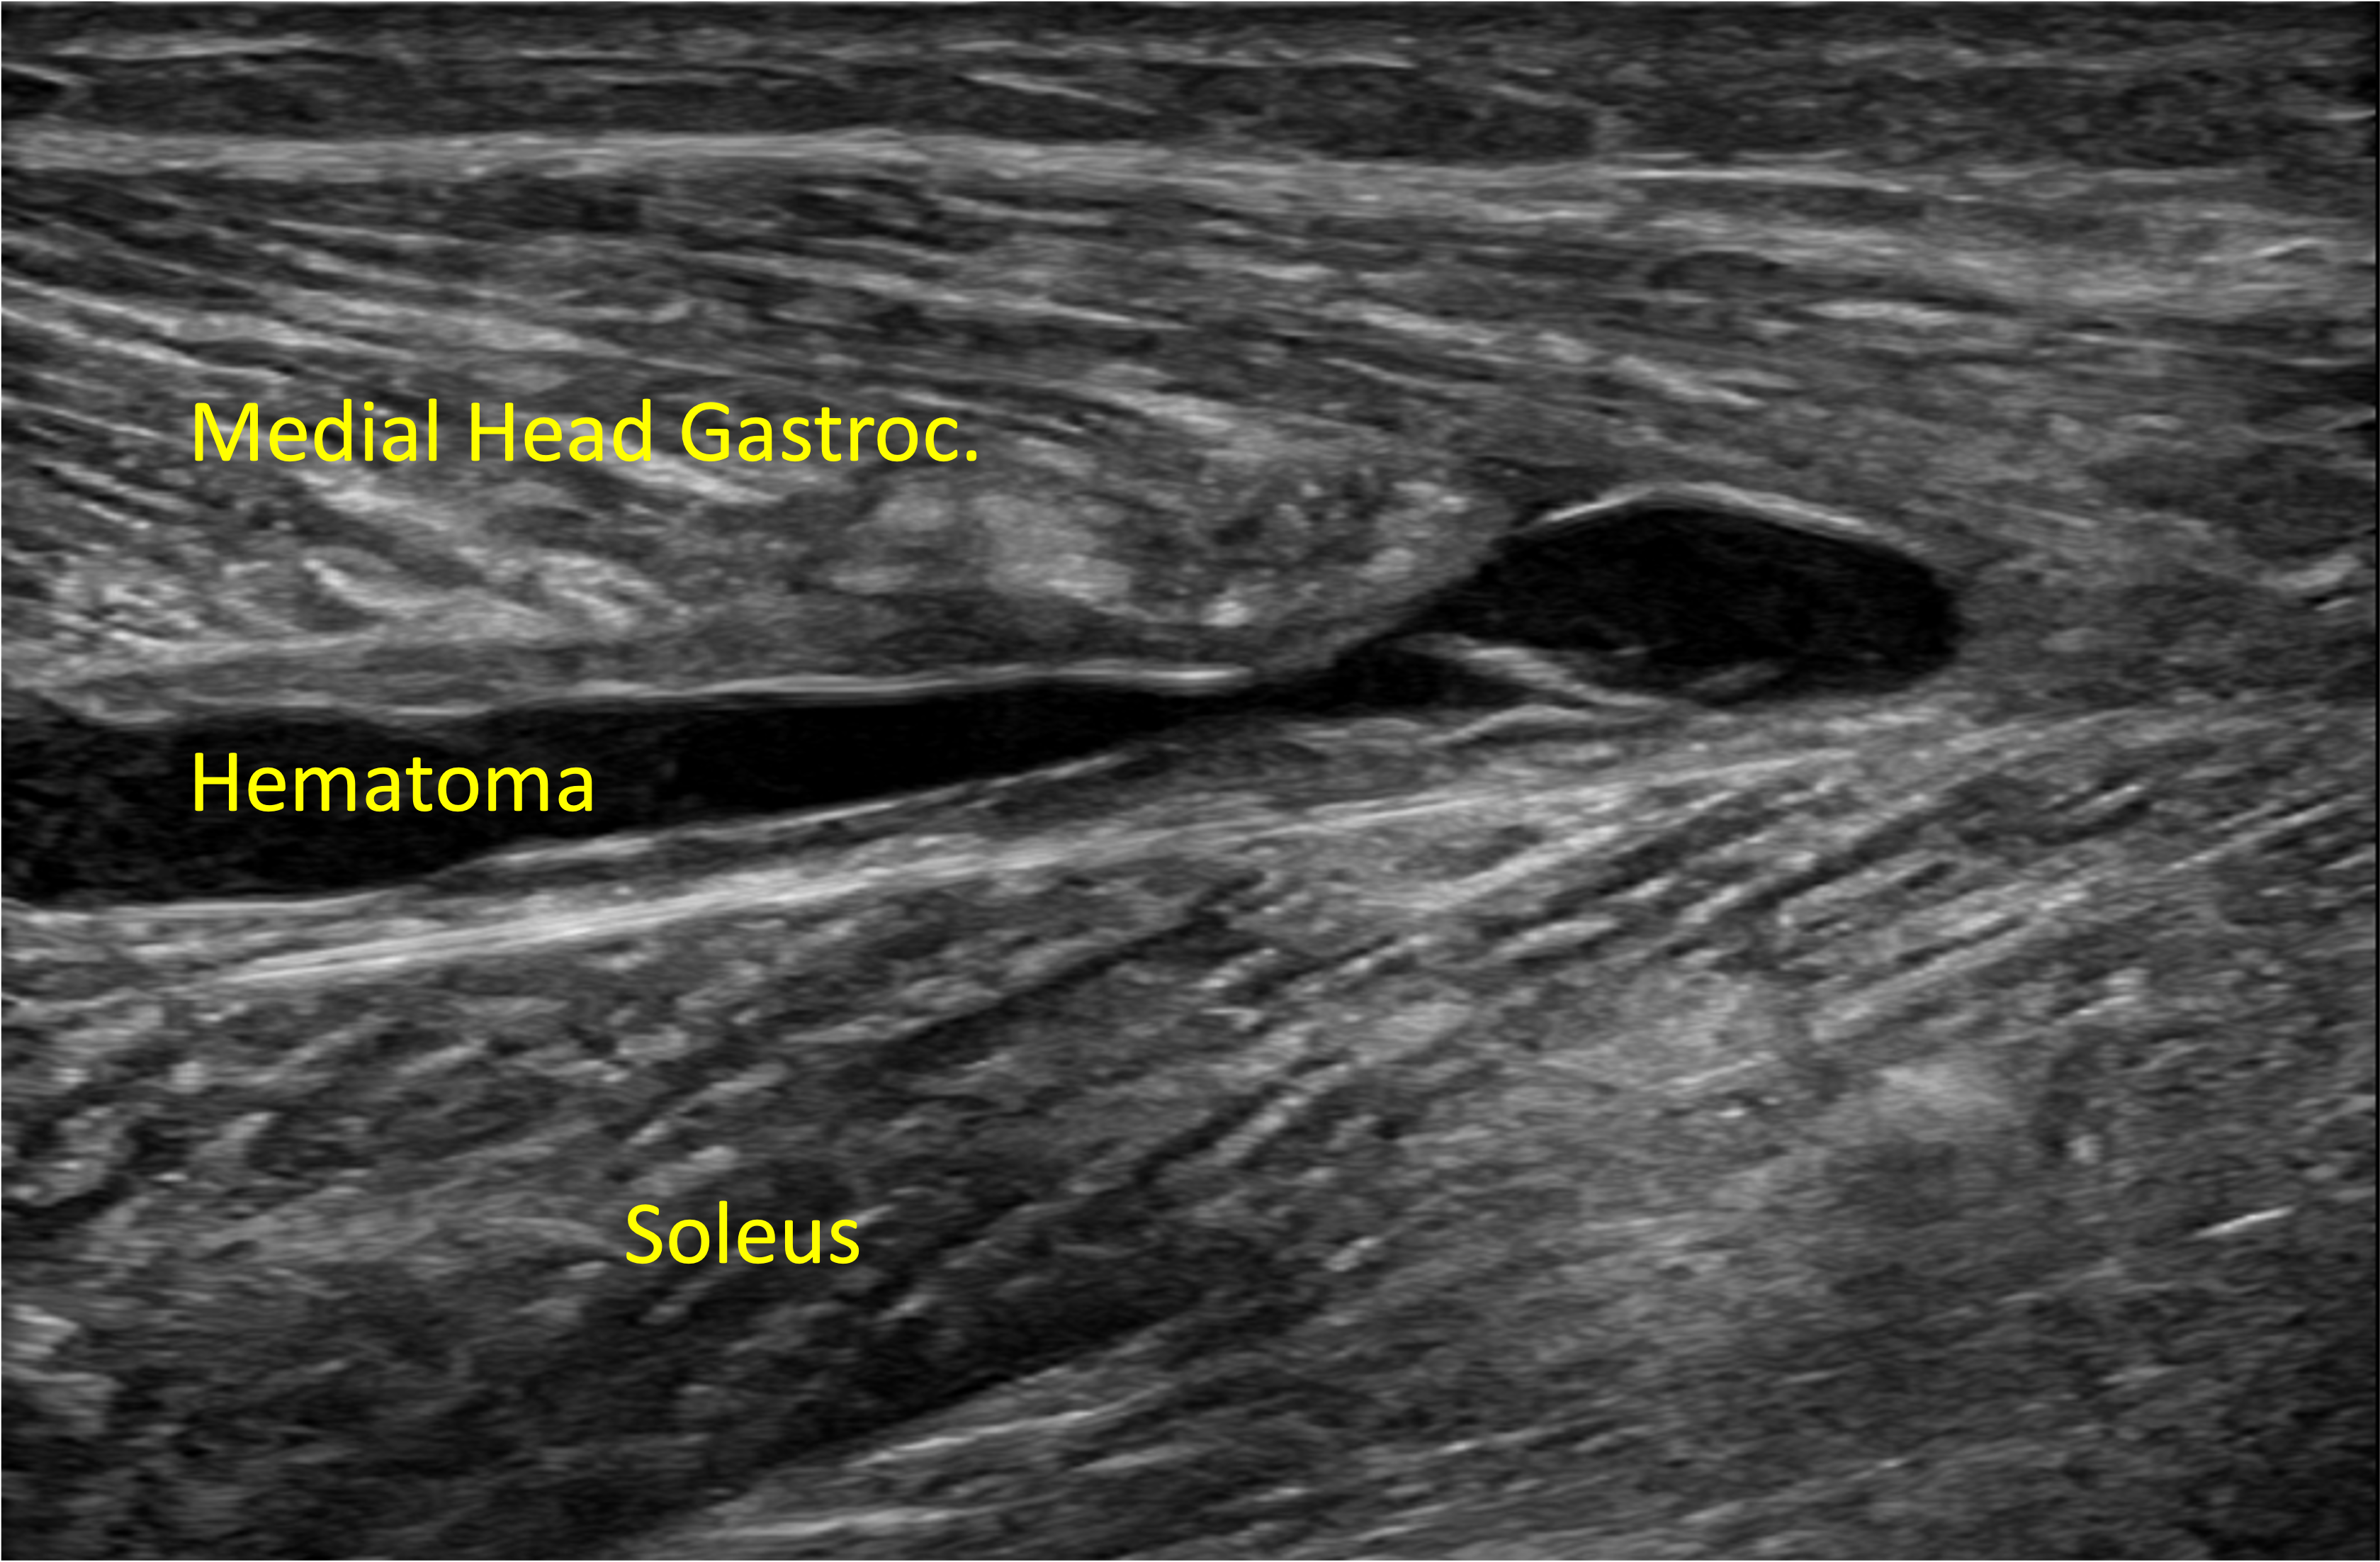

52 yr/M presented with painful calf swelling for 3 weeks. He had experienced a sudden & shooting calf pain during a game of badminton.

Ultrasound (US) imaging shows discontinuity of the medial head of gastrocnemius (MHG) muscle fibers at the distal myoaponeurotic junction resulting in a partial thickness tear. A liquified hematoma is seen tracking between the soleus & medial head of gastrocnemius muscle bellies. The Achilles tendon appears intact.

US imaging is a useful tool in the diagnosis and management of muscle tears & ruling out deep venous thrombosis. It can help to identify the exact site (intramuscular, myo-tendinous junction, myofascial junction) of the muscle tear, length of tear, muscle retraction & presence of an associated hematoma. These factors can predict the athlete’s return to play time.